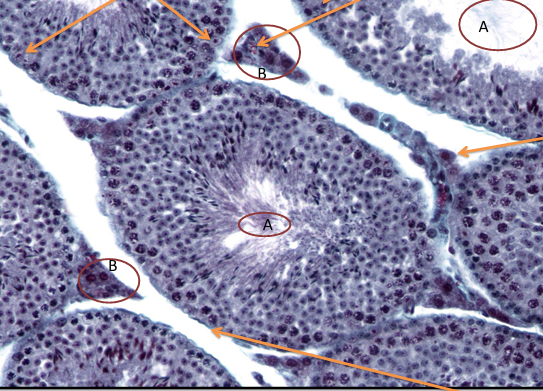

jądro nr 414

światło kanalików nasiennych

błona podstawna z komórkami mioidalnymi otacza

jądra komórki sertoliego

komórki germinalne

naczynie włosowate w interstycjum

tkanka interstycjalna z komórkami Leydiga